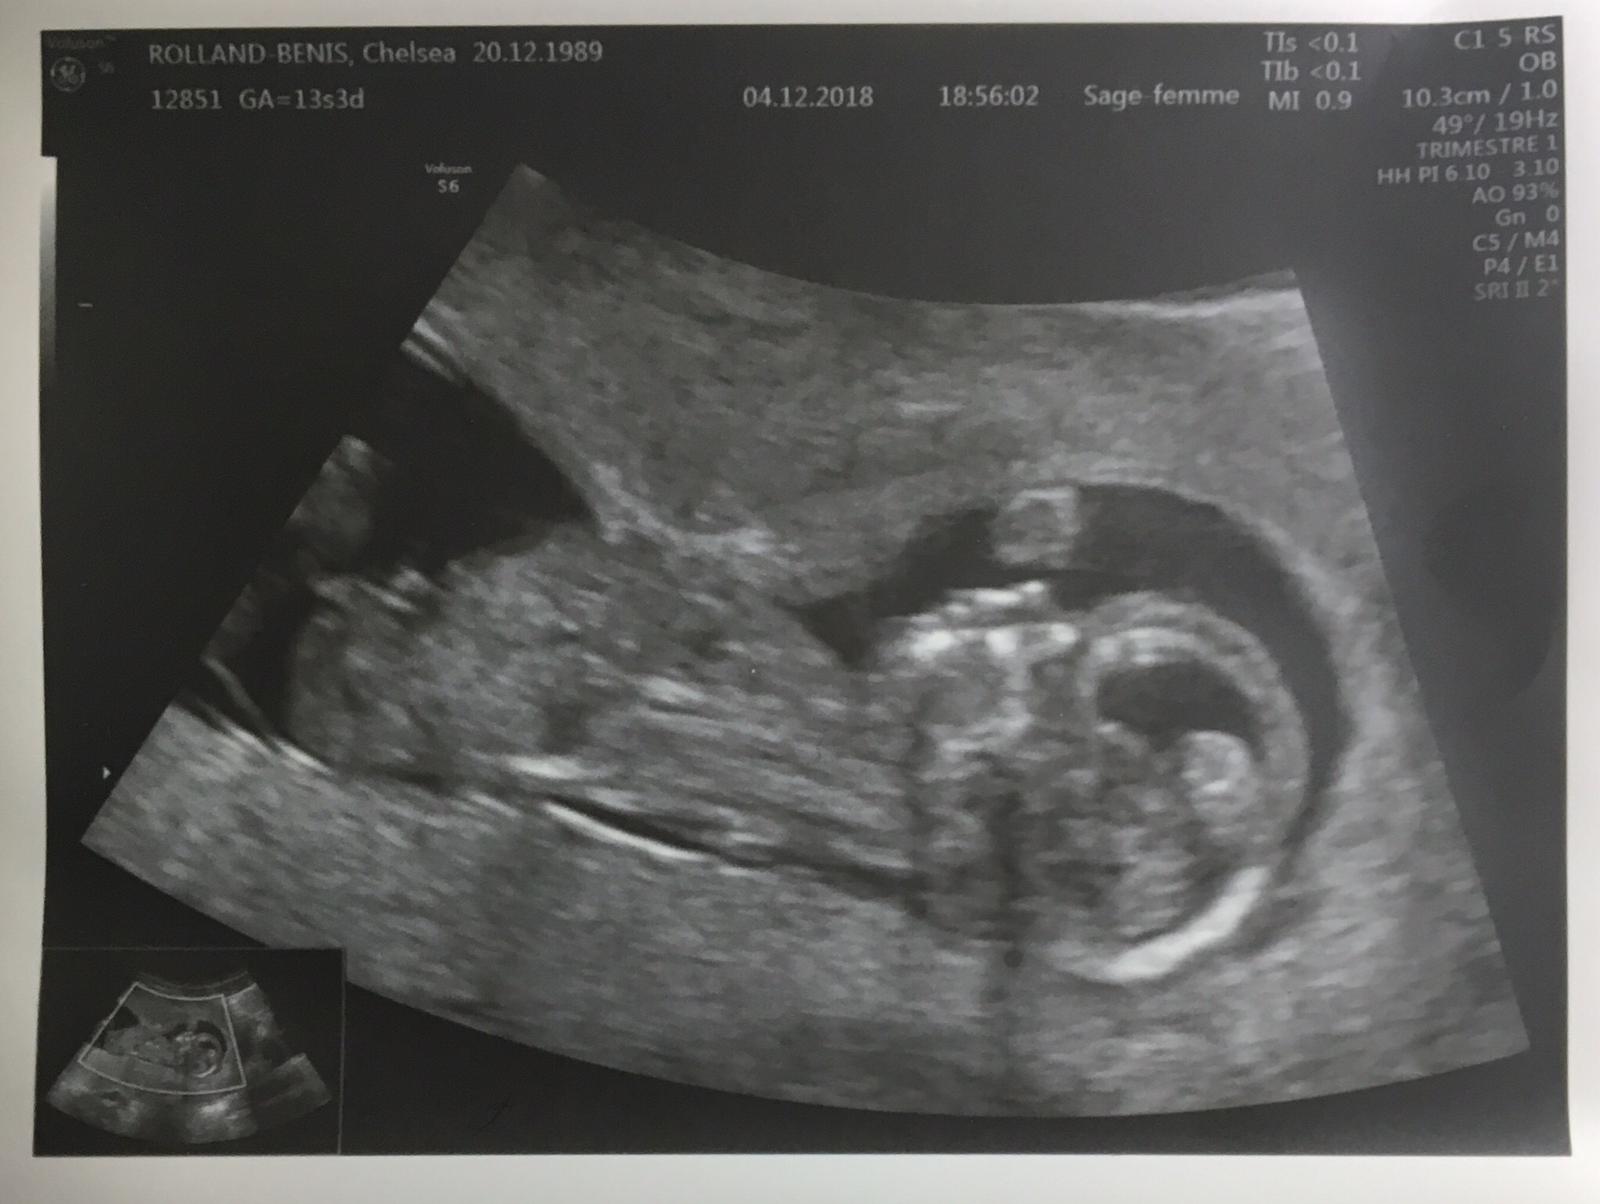

Meet baby to be.

Do you see the profile?

Due date is the early part of June 2019.